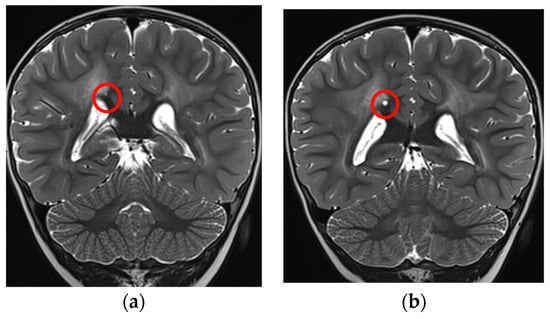

Moreover, there was an intercurrent millimetric dimensional increase of the small cystic formation along the right margin of the splenium of the corpus callosum that showed a subsequent reduction at the last brain MRI, performed without sedation with a “quick MRI protocol” (Figure 4a,b).

Figure 4. Coronal T2-TSE showing a slight increase in dimension of the cyst (red circles): (a) 2 years and 4 months of age, (b) almost 3 years.